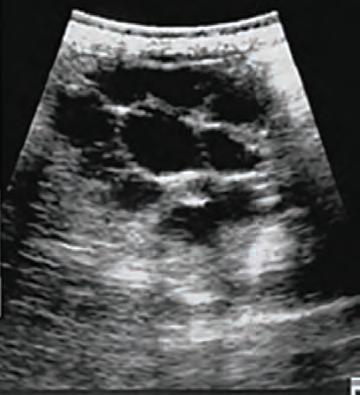

Veterinary assessment should begin with a detailed history and behavioural description, followed by a reproductive examination. Transrectal ultrasonography of the uterus and ovaries can help determine the condition of the uterus and allow comparison of the ovaries for size, texture and structures present.

This is often done in conjunction with an AMH blood test in suspect GCT cases as this is the most specific diagnostic test with 98% accuracy reported.